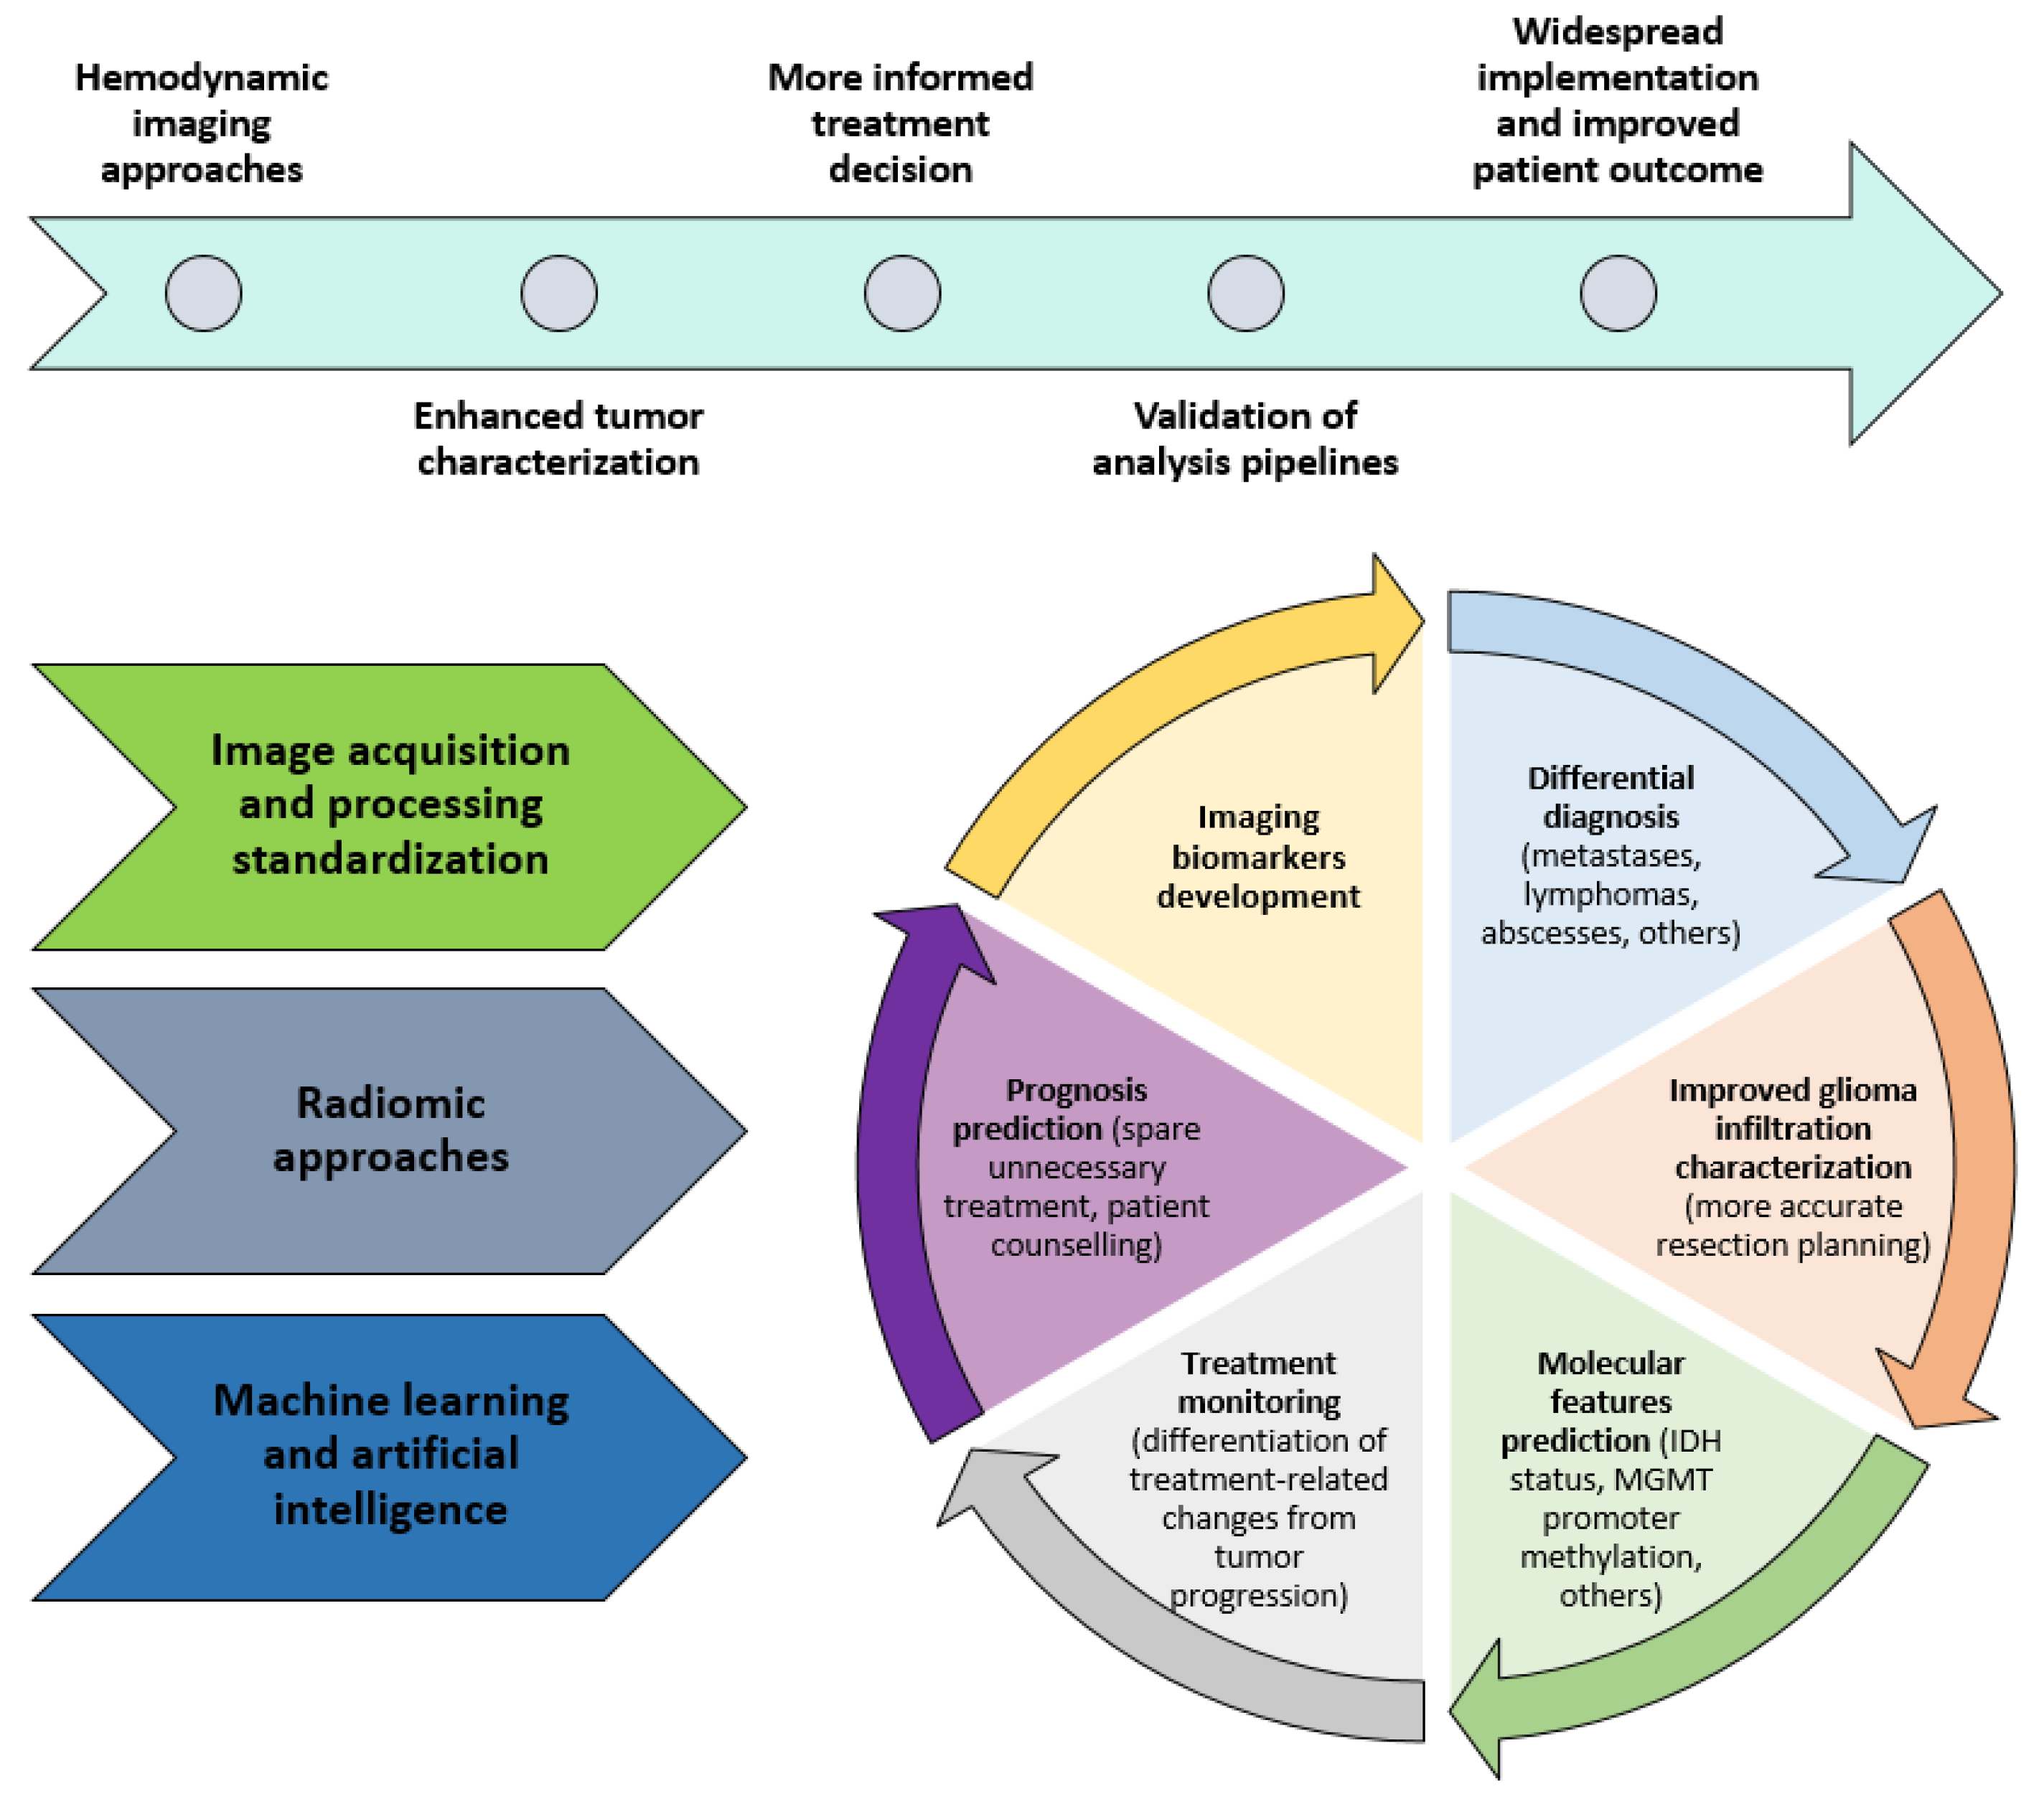

3. Future Directions

3.5. Machine-Learning and Radiomics

4. Conclusions